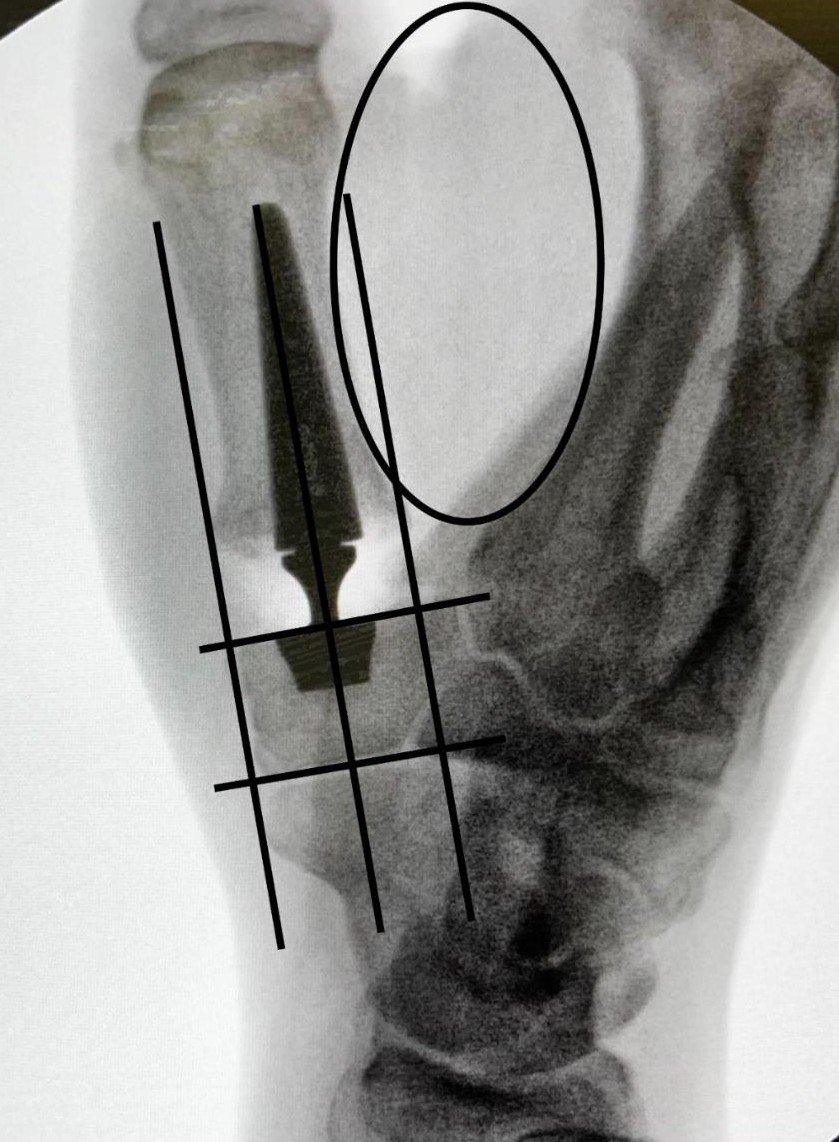

Touch® CMC Prosthesis Touch CMC dual mobility prosthesis X-ray in thumb joint

Dual Mobility Standard

Touch® CMC Prosthesis

🛡️ Anti-Dislocation ⚙️ 144 Combinations

The gold standard for CMC arthroplasty, restoring thumb function with a unique dual-mobility design.